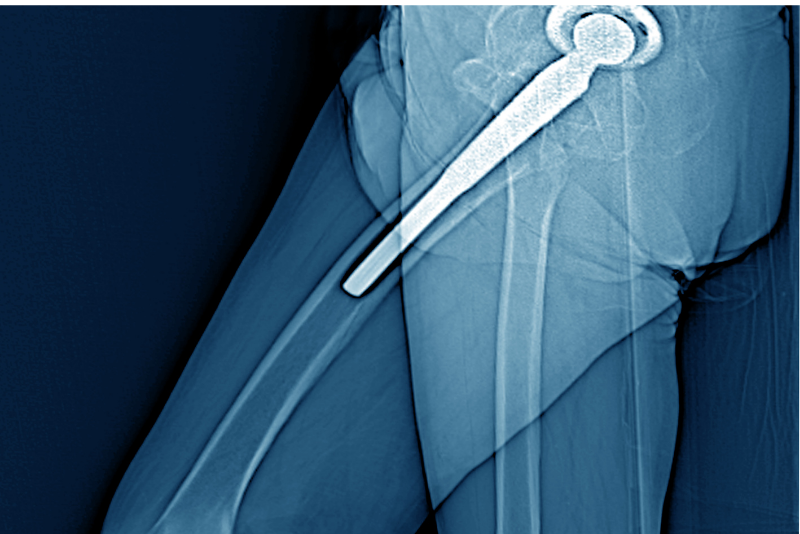

Kalça cerrahisi kapsamında en sık uygulanan prosedürlerden biri total kalça protezi ameliyatıdır. Kalça ekleminde geri dönüşü olmayan hasarlar oluştuğunda ve konservatif tedavi yöntemleri yetersiz kaldığında, hasarlı eklem yüzeyleri özel protez implantlarıyla değiştirilir. Bu işlem, hastaların ağrısız bir şekilde hareket etmelerini sağlarken, eklemin doğal işlevlerini yeniden kazanmalarına yardımcı olur. Günümüzde kullanılan gelişmiş protez teknolojileri sayesinde, protezlerin dayanıklılığı artmış ve hastaların daha uzun yıllar konforlu bir şekilde hareket etmeleri mümkün hale gelmiştir.

İleri düzey eklem hasarı ve kireçlenme durumlarında, kalça eklem yüzeyini değiştirmeye yönelik cerrahi yöntemler devreye girer. Kalça protezi ameliyatı, kalça ekleminin hasarlı kısımlarının yapay protezlerle değiştirilmesini içerir ve hastaların ağrısız bir şekilde hareket etmelerini sağlayarak yaşam kalitesini önemli ölçüde artırır. Bununla birlikte, kalça kırıkları da özellikle ileri yaş gruplarında sık görülür ve cerrahi müdahale gerektirebilir. Kırık tipine bağlı olarak vida, plak veya protez uygulamaları ile hastaların hareket kabiliyeti geri kazandırılabilir.